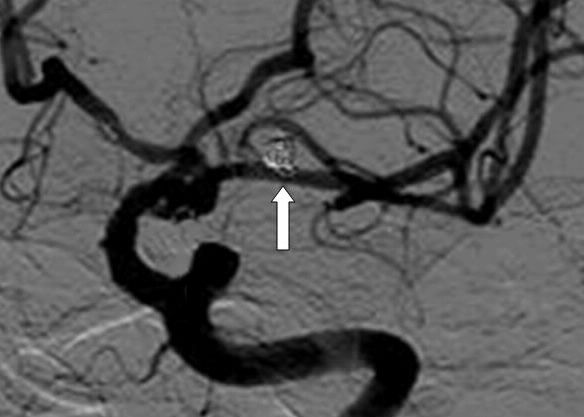

1.女、71岁、半年内两次SAH,头CT:SAH,Fisher 1级,H-H 2级。

额极动脉与M1成反折的锐角,多次微导管塑形技术超选失败,后使用成袢技术顺利超选。

微导管在M1段成“∝”状,微导丝超选进瘤腔。

此时与常规操作不同,不是前推而是回撤微导管,随着微导管进入瘤腔,同步撤微导丝进入微导管内。

恰如足球的倒钩射门一样。

顺利栓塞动脉瘤。